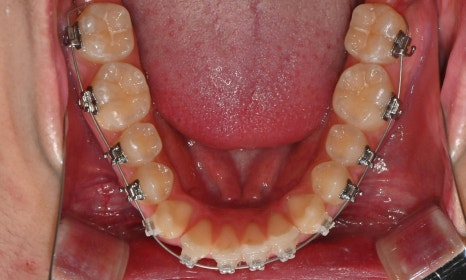

치료 시작 7개월 후 - 연세정원치과

치료 시작 7개월 후 사진으로, 치아 배열 후 아래 우측에 미니스크류를 식립하여 치아 중심선을 개선하는 중으로, 교합과 치아 중심선이 많이 개선된 것을 확인할 수 있습니다.